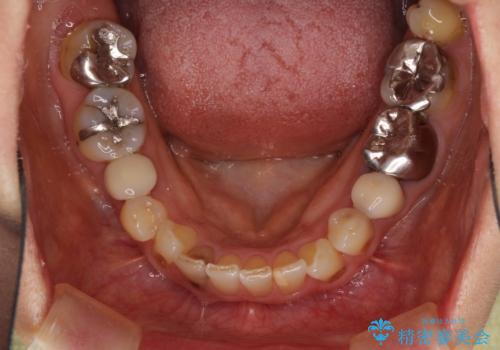

- 目立つ銀歯を気にして来院された患者様です。

奥歯を中心に銀歯が多く装着されており、一部の歯は咬合時に痛みを感じている状態でした。

必要な歯に根管治療を行い、オールセラミッククラウンにて補綴治療を行うこととしました。